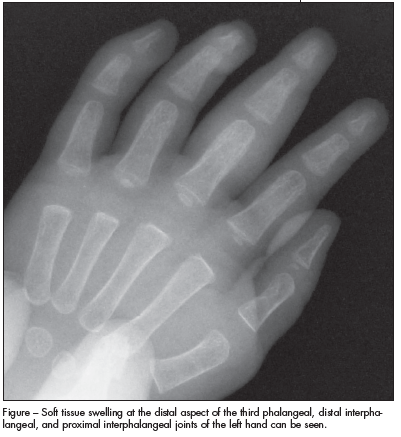

For 2 to 3 weeks, a 10-year-old boy had pain and swelling of the left ankle.